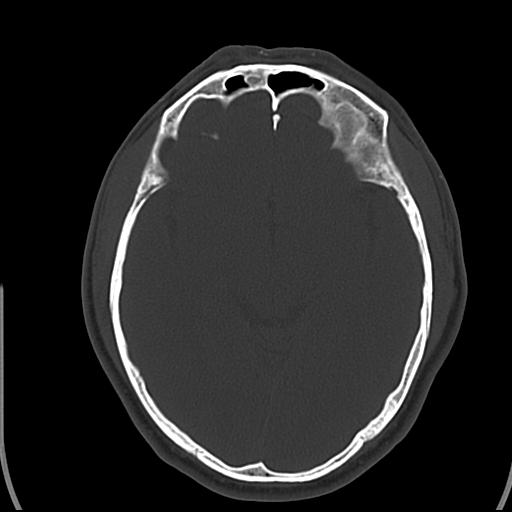

头皮下高密度结节影???临床上在老年男性比较常见。大家看看是什么?成因是? 本例患者,男性,51岁。外伤来诊。无染发史及发根植入史。